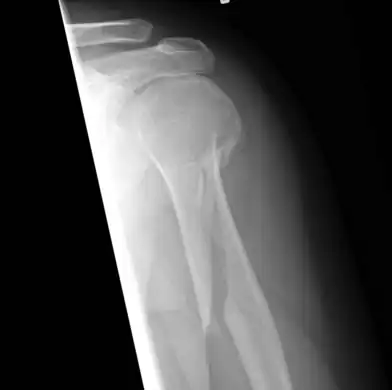

Internal rotation view showing a spiral fracture at junction of middle and distal thirds of humerus.